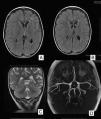

Se realizó un escáner cerebral y un electroencefalograma (EEG) que fueron normales. En la resonancia magnética cerebral (RM) se objetivó un área de alta señal en secuencias T2 afectando a la sustancia blanca paraventricular izquierda, con discreto agrandamiento ventricular y del espacio subaracnoideo hemisférico homolateral (fig. 1A y B). Estos hallazgos sugerían un aspecto residual de la lesión, planteándose como causa un evento isquémico. Fue dada de alta con ácido acetil salicílico y oxcarbacepina con adecuado control de las crisis, persistiendo la hemiparesia derecha.

RMc seriadas mostraron un progresivo agrandamiento ventricular y del espacio subaracnoideo hemisférico izquierdo, persistiendo el área de alta señal en la sustancia blanca (fig. 1C). La espectroscopia fue normal. En la secuencia arteriográfica existía una significativa disminución de ramas distales de la arteria cerebral media izquierda respecto de la contralateral, por lo que se realizó una angiografía cerebral convencional que descartó el origen vasculítico (fig. 1D). Finalmente, se practicó una exploración combinada de tomografía por emisión de positrones (PET) y tomografía computarizada (TC), tras la administración por vía intravenosa de 79 MBq de FDG, donde se observó un hipometabolismo moderado-severo del hemisferio cerebral izquierdo con mayor afectación de la región frontal y temporal (fig. 2).